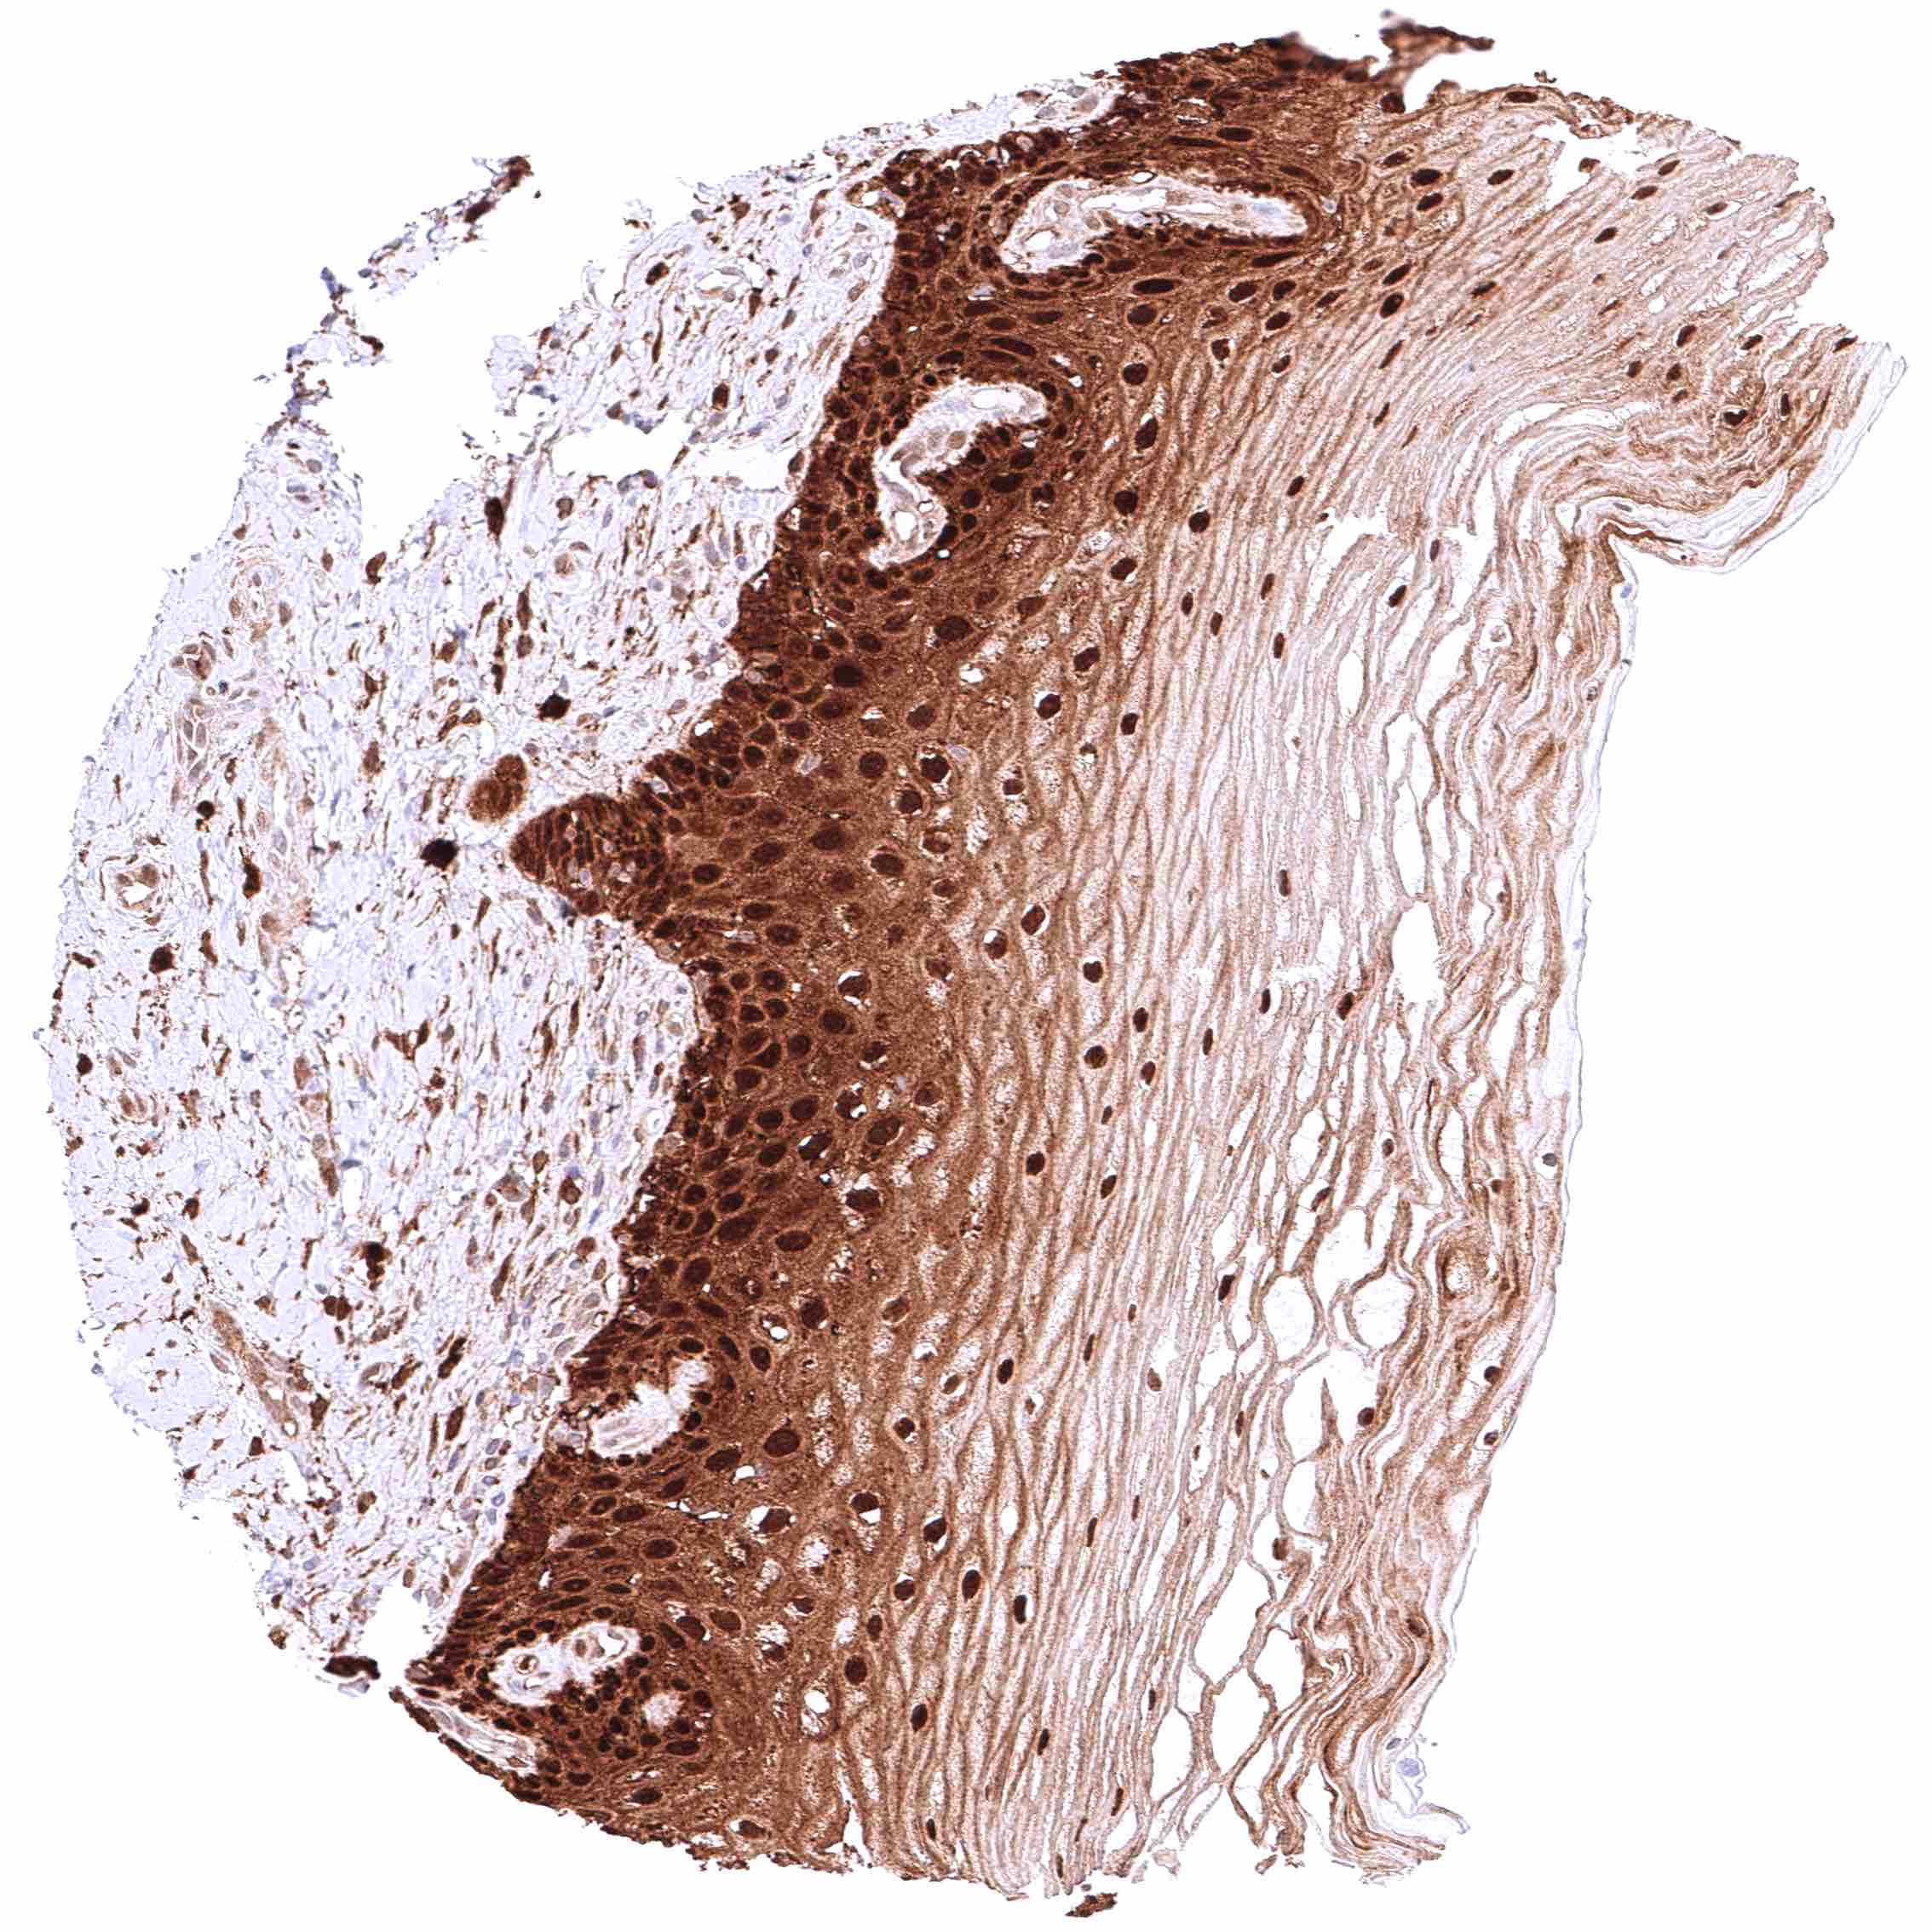

Esophagus, squamous epithelium – Strong cytoplasmic and nuclear GSTP1 positivity of squamous epithelial cells. Staining intensity is highest in the basal and suprabasal cell layers and decreases slightly towards the surface